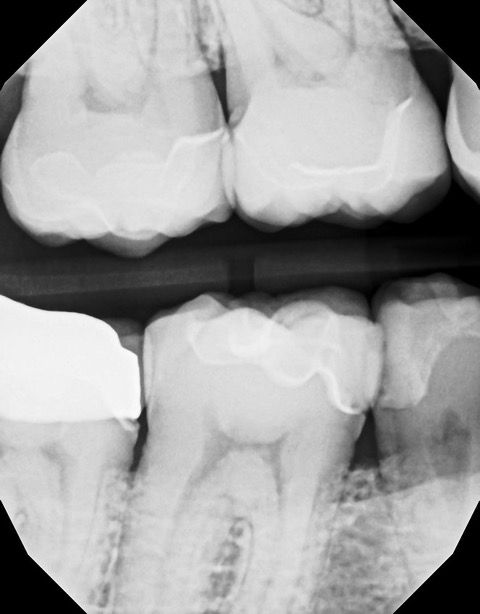

In my own practice, I compared two bitewings from the same patient, one taken with Acuity and one with our existing sensor, using identical exposure settings. The Acuity image immediately stood out. It showed noticeably sharper definition, cleaner contrast, and clearer interproximal visibility. The improvement was visible at a glance and reinforced the diagnostic advantages reported by our evaluators. This kind of image sharpness saves time and reduces retakes.